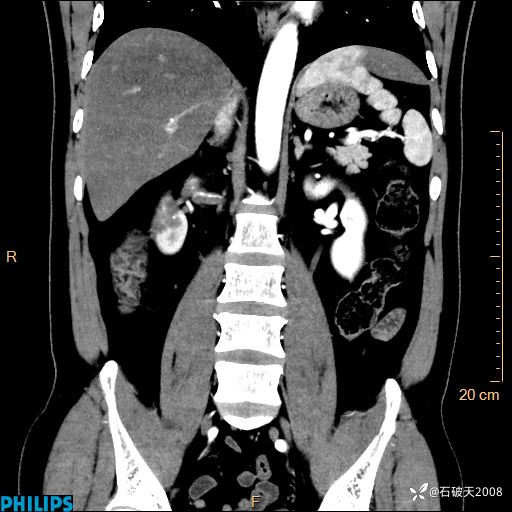

平扫轴位

增强轴位

冠状位